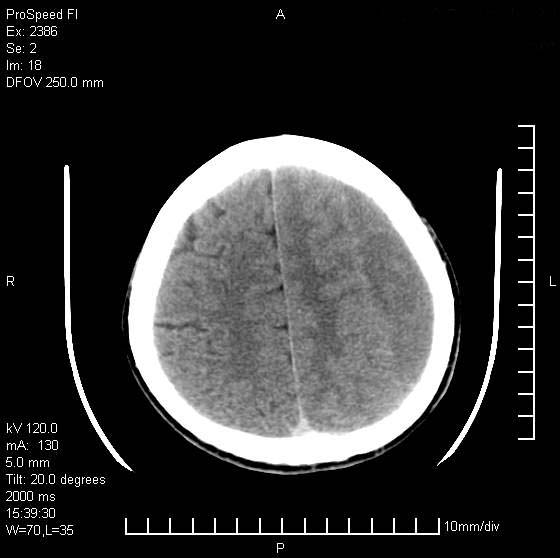

以下是引用天南地北在2007-9-19 18:43:00的发言:[br]典型慢性硬膜外血肿[br][br][本贴已被 天南地北 于 2007-9-19 18:44:11 修改过]

以下是引用曼一拍在2007-9-20 11:06:00的发言:[br]支持慢性硬膜下血肿.[br]慢性硬膜下积液:血肿有包膜,ct值稍高于脑脊液,增强可有染色。不典型者血肿可多呈梭形.是硬脑膜与蛛网膜之间的潜在腔隙内的血肿。[br]鉴别:[br]1\\硬膜外血肿:是颅脑外伤后脑膜或板障内血管破裂,血液在颅骨与硬膜之间积聚所致.通常是脑膜动脉破裂,也可因静脉窦破裂或颅骨的板障静脉出血,发生于外伤的着力部,常与颅骨骨折并存。脑膜动脉出血则急,若是板障静脉出血在则可有慢性。[br]2\\硬膜下积液:(硬膜下水瘤)[br]是由于蛛网膜破裂,脑脊液经蛛网膜破口进入硬膜下腔不能回流。或水肿阻塞而形成。[br]ct表现:颅骨内板下方新月形低密度区近似脑脊液密度;占位效应清,周围无脑水肿。[br]